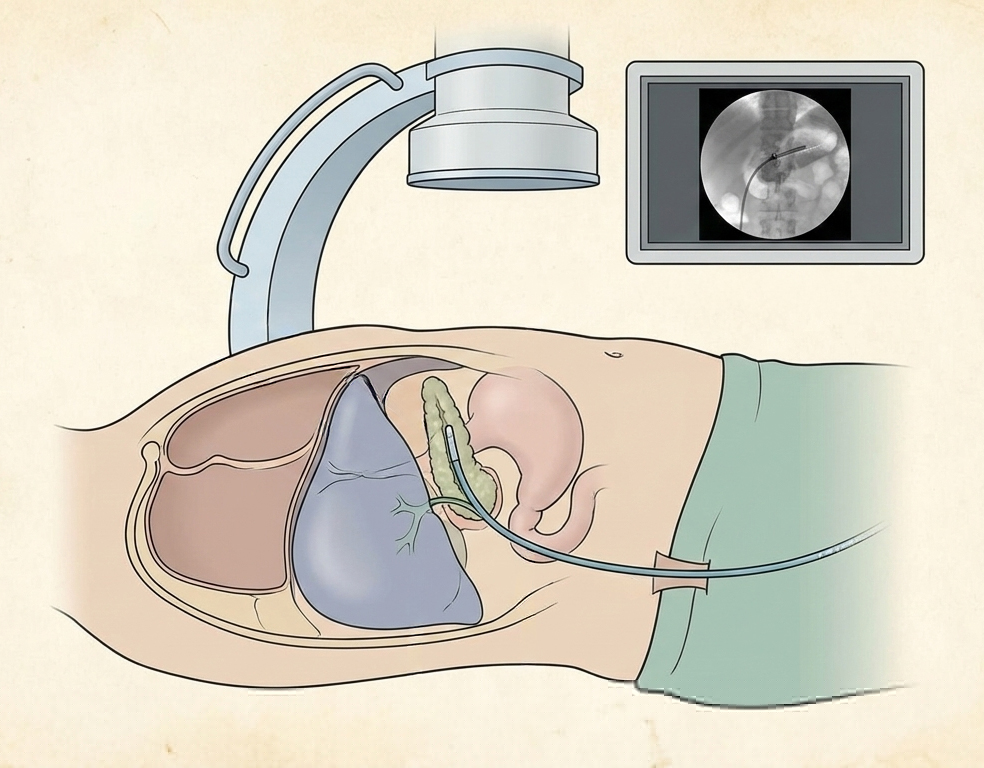

- Percutaneous Biliary Drainage. If endoscopic access is impossible, such as in cases of tumor-related duodenal narrowing, or if endoscopic attempts fail, the guideline endorses PTCD (percutaneous transhepatic cholangiodrainage) as a viable alternative.[20]